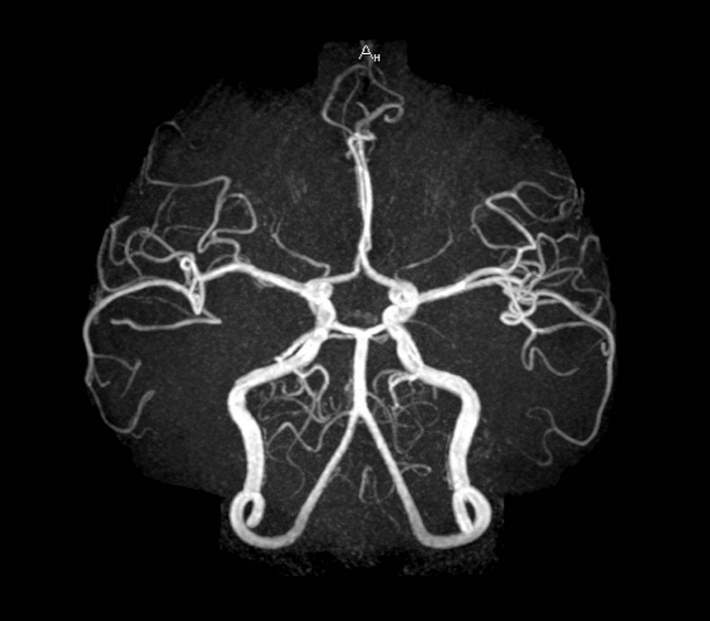

急诊脑血管cta检查提示:左侧椎动脉急性闭塞,血管内可见大量血栓形成

彩色多时相ct血管成像(colorviz mcta)在急性脑缺血性卒中患者中的

急性脑血管闭塞,6小时内抓住生命的绳索

脑血管cta临床应用(1)

脑血管cta临床应用(2)